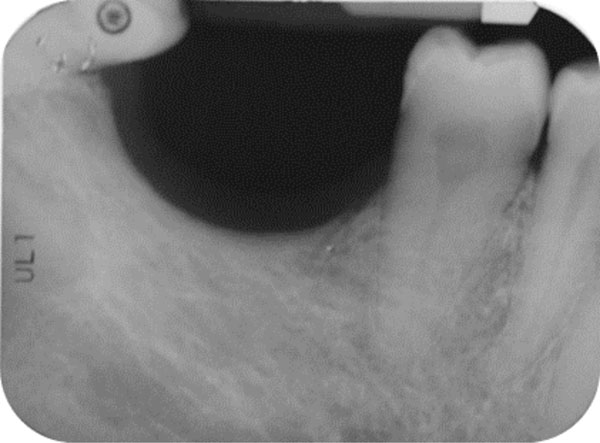

The patient was a non-smoking, 55-year-old man with a non-contributory medical history who presented seeking to improve his masticatory function on the lower right side of his mouth. A comprehensive intraoral examination was performed to assess his overall oral health. The patient was missing teeth 46 and 47 (Fig. 1a, 1b); clinical and radiographic examination revealed a severe vertical defect of the corresponding alveolar ridge (Fig. 2). After assessing the periodontal status of the adjacent teeth, a treatment plan was developed calling for a GBR procedure and simultaneous placement of a dental implant. The patient provided informed consent.

Endoral radiograph. The corresponding alveolar ridge shows a severe vertical atrophy.